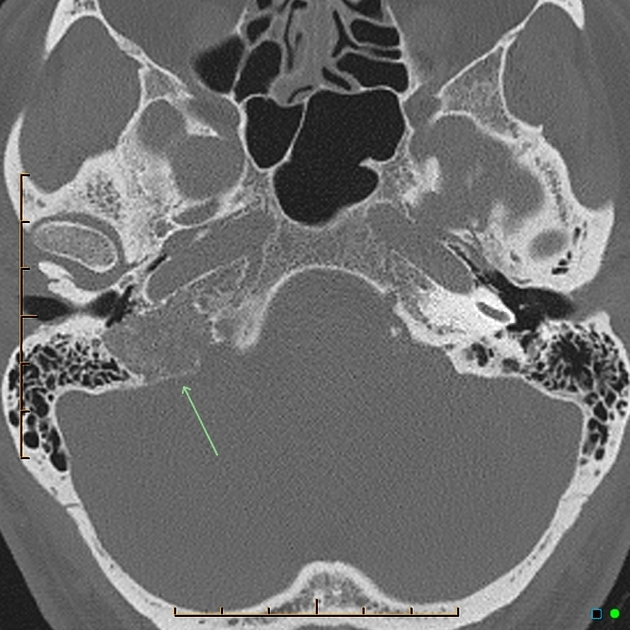

Jugular paraganglioma or Glomus jugulare (Source: Radiopaedia.org)

Glomus tumors in the ear, nose, and throat (ENT) region are rare, benign growths that can significantly impact a patient’s quality of life. These tumors typically develop in the middle ear, temporal bone, or along the jugular vein.

2. Glomus jugulare: Found near the jugular bulb

Diagnosing glomus tumors in the ENT region typically involves:

• Imaging studies (CT scan, MRI, and sometimes angiography)